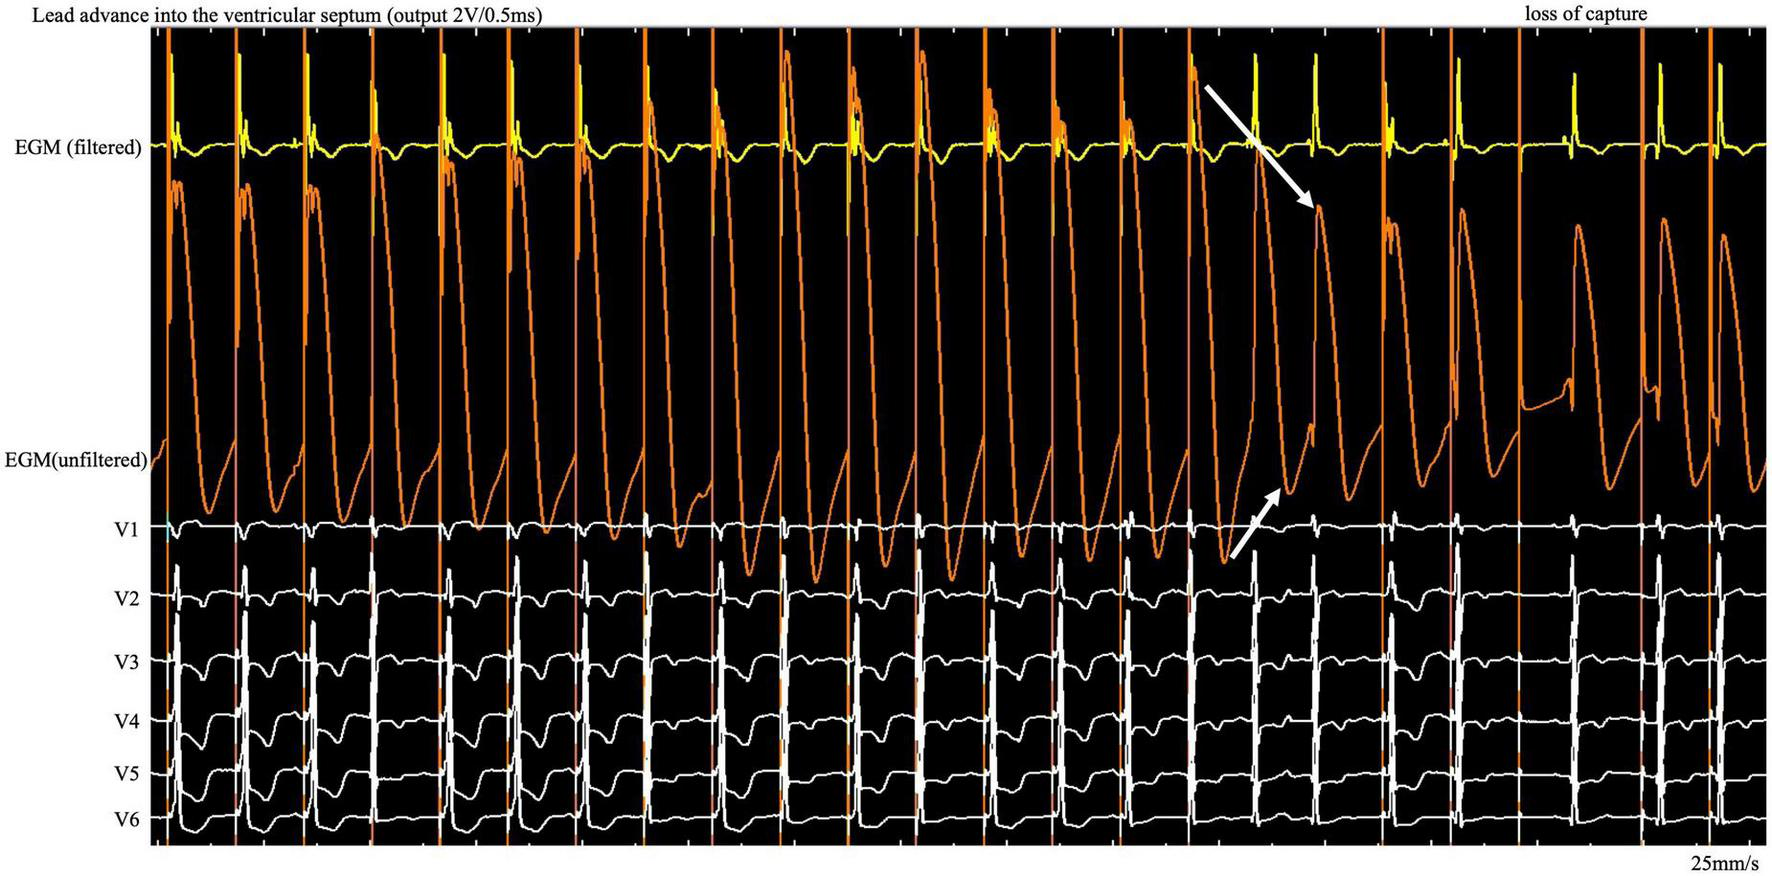

A 76-year-old woman with atrial fibrillation and third-degree atrioventricular block underwent LBBP. Echocardiography examination revealed left ventricular end-diastolic diameter of 44 mm and left ventricular ejection fraction of 75%. Uninterrupted ECG and EGM were recorded on an electrophysiology system using John Jiang’s connecting cable (Xinwell Medical Technology Co., Ltd., Ningbo, Zhejiang, China) (5, 6). In contrast to the interrupted pacing method, this continuous pacing and recording technique enables real-time monitoring of changes in ventricular COI and the paced QRS complex as the lead advances into the interventricular septum. We previously described the LBBP implantation procedure in detail (7, 8). During the entire screw-in process, the COI amplitude increased, peaked, and gradually decreased, followed by a small but significant abrupt decrease (Figure 1). Simultaneously, the impedance dropped from 691 to 532 Ω, and the myocardium capture was lost. This indicates septal perforation. No transition from left ventricular septal pacing to non-selective LBBP (NSLBBP) or NSLBBP to selective LBBP was observed during implantation. With no evidence of LBB capture, the electrode was retracted for the second implant. Repositioning to another site was uneventful. Smooth transition of paced QRS morphology from the LBB block pattern to the right bundle branch block pattern was observed as the lead advanced from the right to left side of the septum. After the COI amplitude peaked, the electrode was rotated very slowly to avoid a sudden drop in COI until the LBB area was reached. An abrupt shortening of the V6 R-wave peak time (V6RWPT) and a discrete EGM were subsequently observed (Figure 2), indicating LBB capture (9). The pacing threshold at the end of procedure was 0.7 V/0.5 ms. The lead was placed at a depth of 14 mm (Supplementary Figure).

FIGURE 1

During the entire screw-in process, the COI amplitude increased and then decreased gradually after reaching the peak, followed by a small but significant abrupt decrease. COI, current of injury; ECG, electrocardiogram; EGM, intracardiac electrogram.

Here we found a gradual increase in COI, followed by a gradual decrease, as the lead was gradually screwed into the septum. The possibility of microperforation should be considered after a small but significant, rather than dramatic, decrease in COI amplitude and the existence of impedance decrease with myocardial capture loss on unfiltered unipolar EGM (Figure 1, white arrow). Lead rotation should be stopped immediately to avoid complete entry into the ventricular cavity. The screw site must be repositioned, and the pacing output testing must be repeated in the same manner. The continuous pacing and recording technique in clinical practice allows real-time monitoring of the entire perforation process and early termination of the helix screwing to prevent immediate complete septal perforation in the event of a small and abrupt COI decrease.